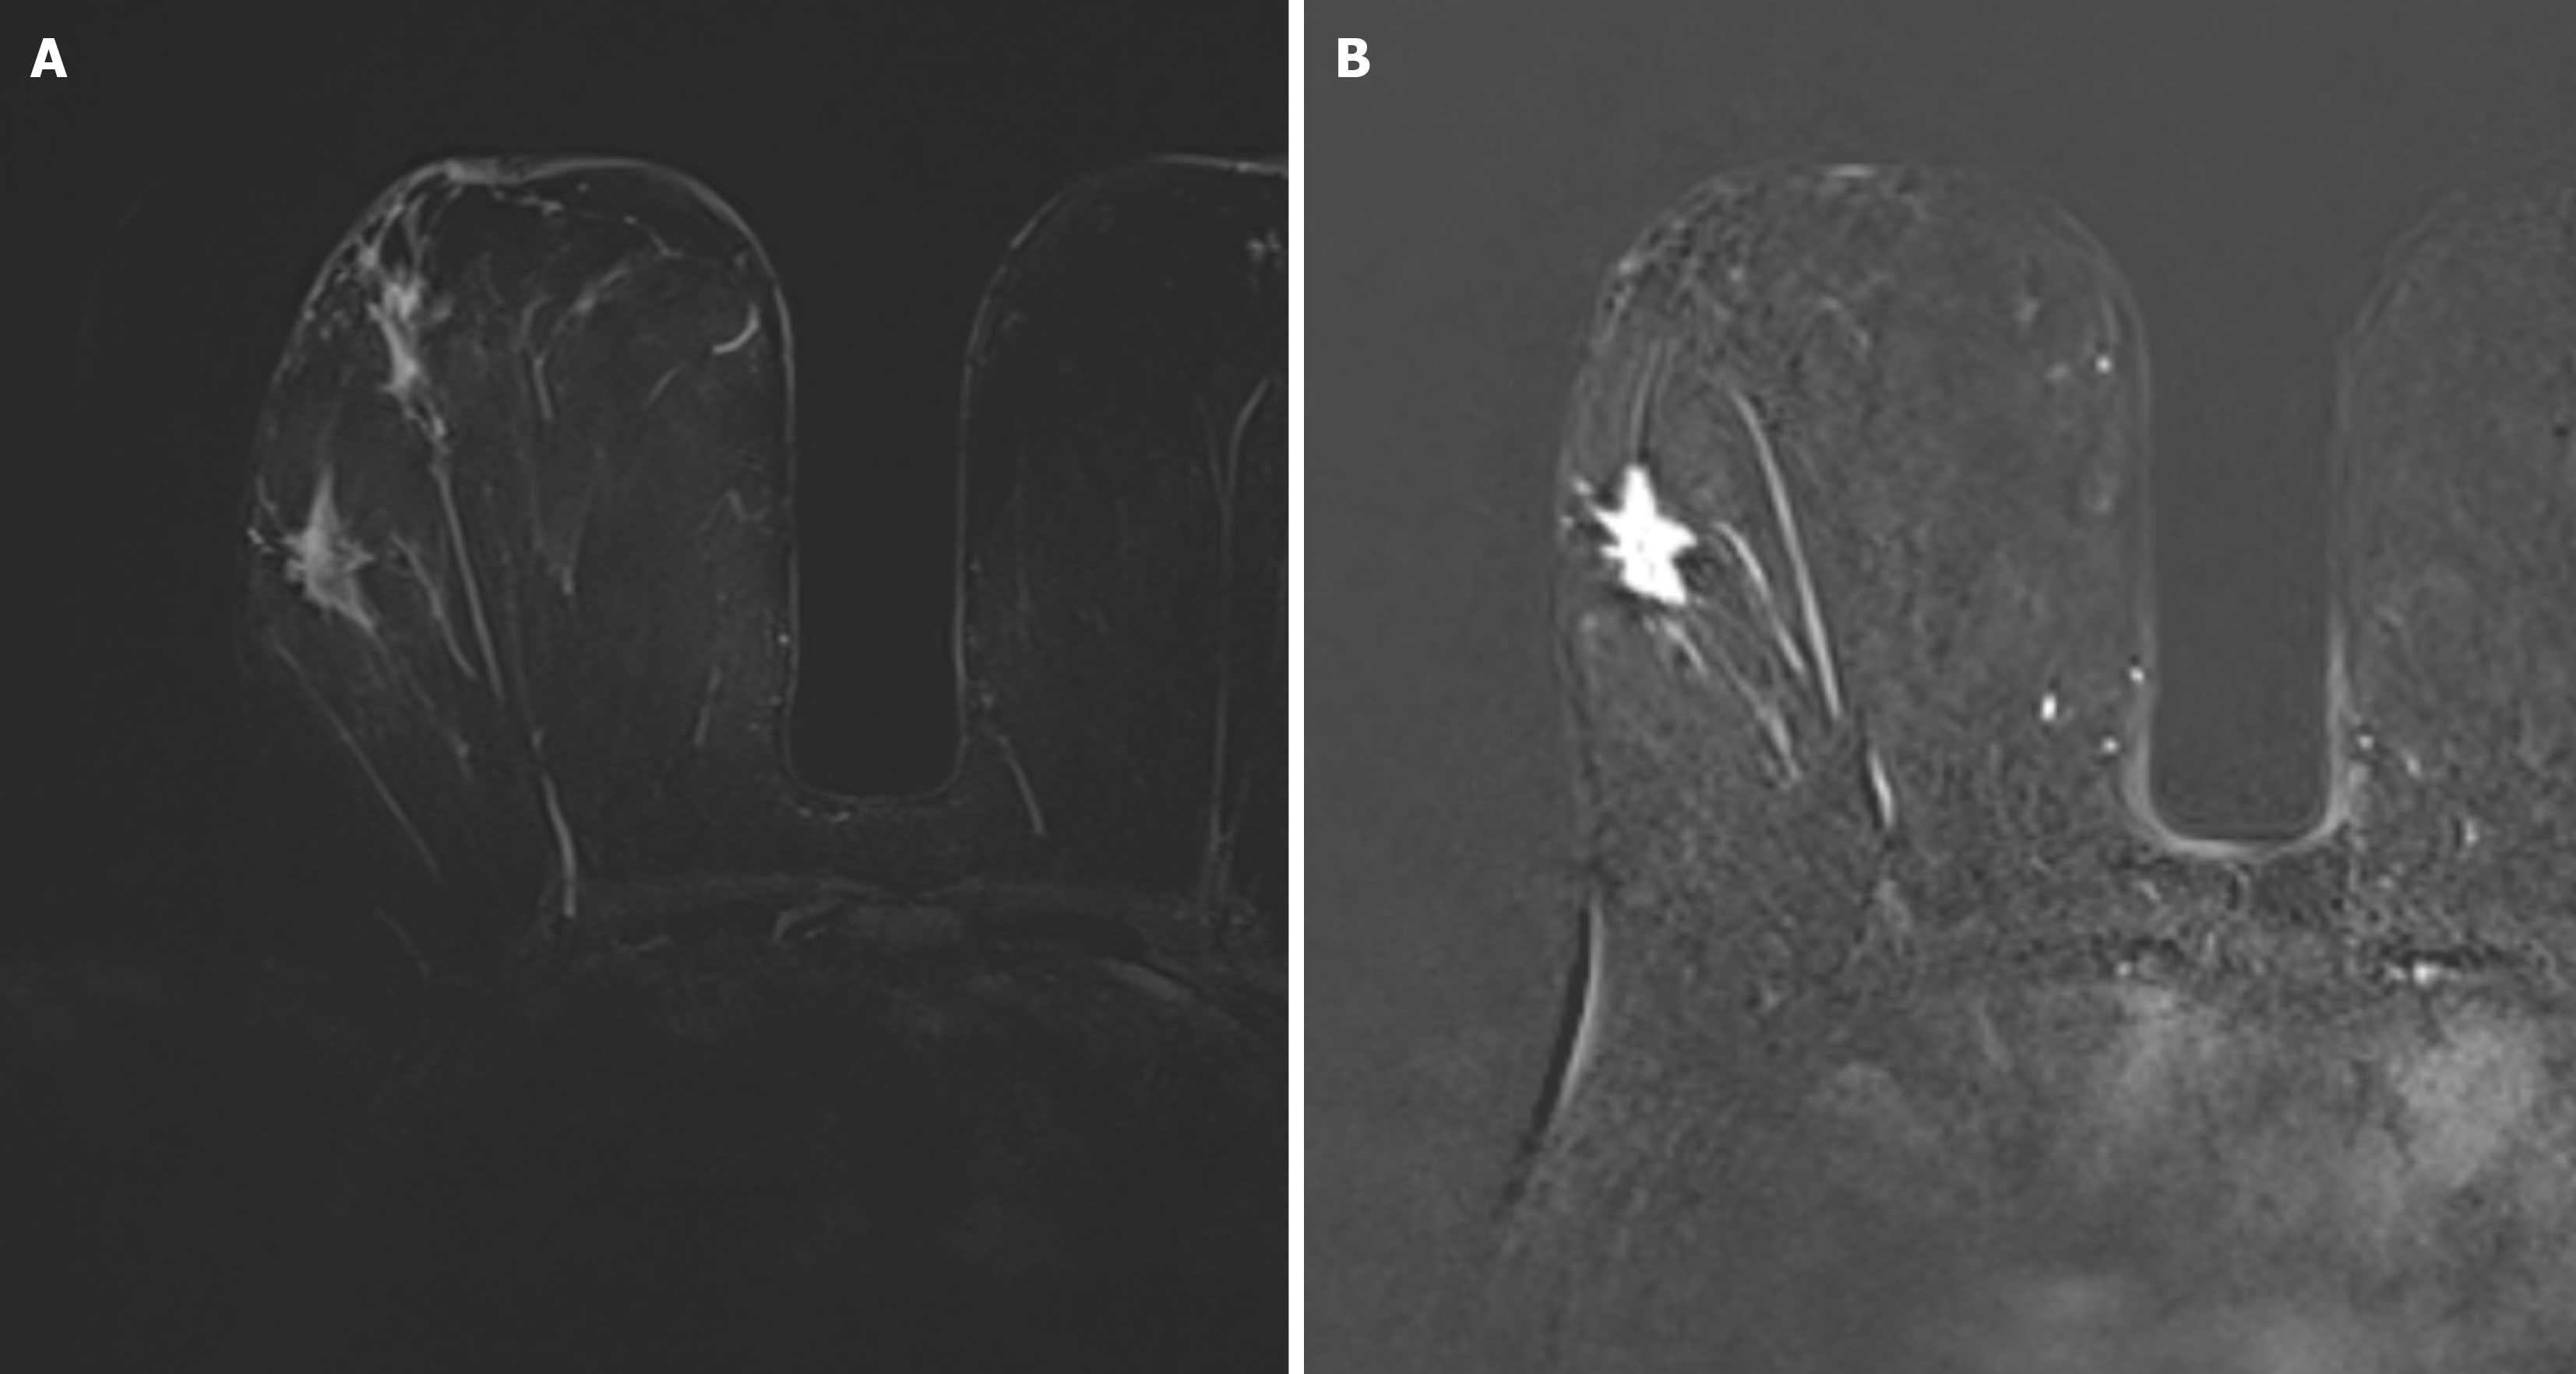

Figure 2 A 56-year-old woman with right breast invasive ductal carcinoma-no special type, triple-negative breast cancer.

A: Axial turbo inversion recovery magnitude image shows peritumoral edema without contrast enhancement on; B: Axial subtraction images.